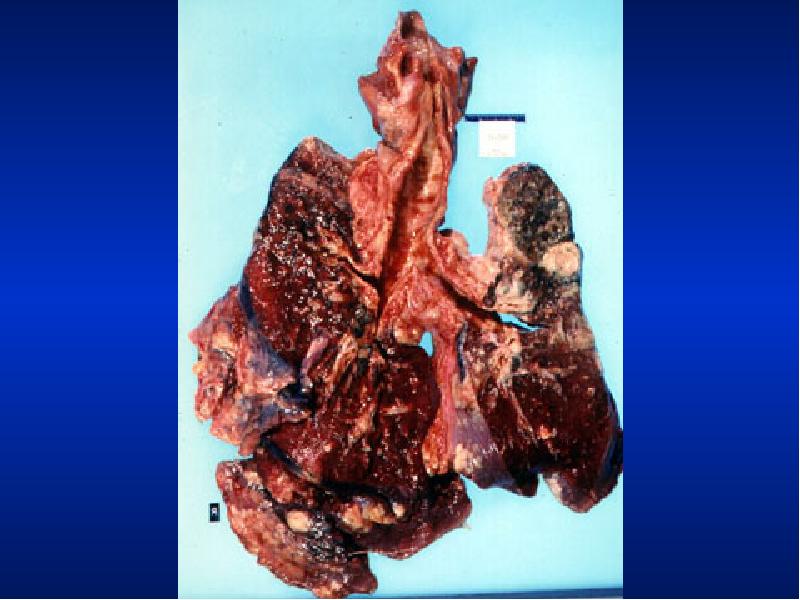

- 5. Illustrative Pathological problems Consolidation Atelectasis Pleural effusion Pneumothorax Mass Diffuse lung